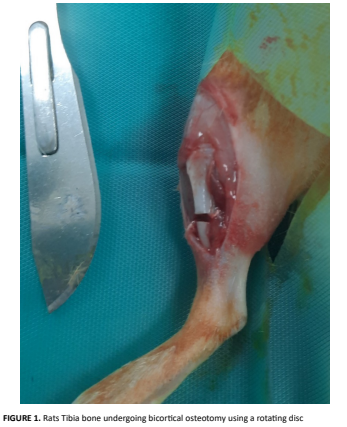

Medicina Veterinaria - Reporte de Caso